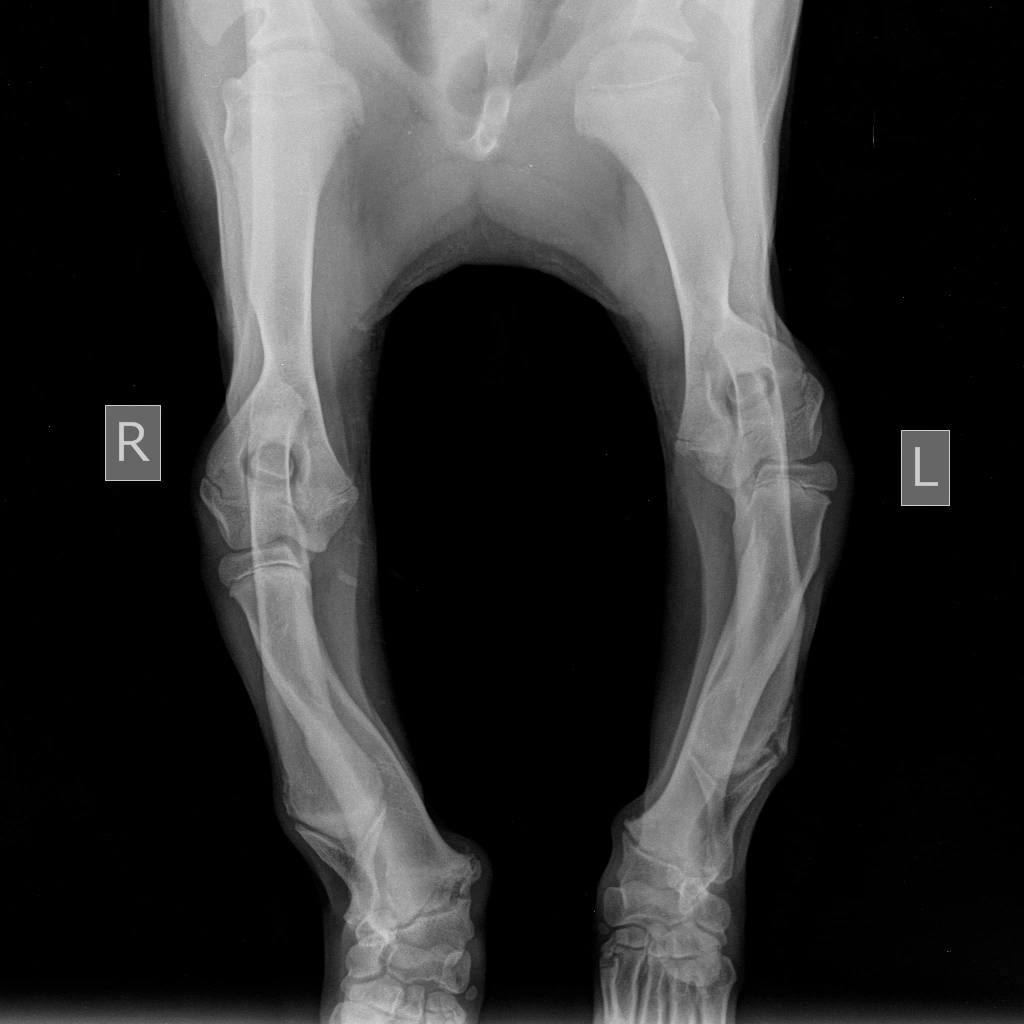

Предплечье состоит из двух костей (лучевой и локтевой), в норме они развиваются синхронно. При заболевании отмечается раннее закрытие зоны роста локтевой кости, что останавливает ее рост, в то время как лучевая кость продолжает увеличиваться в длину. Дальнейшему росту кости препятствуют локтевые и запястные суставы, что вызывает избыточное давление на них и искривление самой кости. Патологическое давление на сустав вызывает развитие дегенеративного изменения хряща (артроза, артрита, остеоартрита).

Основными клиническим признаками является нарастающая хромота и искривление лап в области запястья (так называемый «размет лап», а также припухлость в области локтевого сустава и его малоподвижность).

Диагноз ставится на основании анамнеза, ортопедического осмотра и инструментальных методов диагностики, таких как рентгенография и компьютерная томография (КТ), при которых врач может оценить стадию заболевания и выбрать подходящую тактику лечения.

Если данные виды хирургического лечения не оказывают достаточно хорошего эффекта, т.е. у животного наблюдается хромота и присутствует визуальные различия между передними конечностями, то прибегают к такой хирургической методике как корректирующая остеотомия лучевой кости. Но данная методика может быть использована только после окончания роста костей в длину (10-12 мес.) При данной методике разрезают (метод открытого клина) либо вырезают участок лучевой кости (метод закрытого клина) и место остеотомии фиксируют накостной пластиной или внешним фиксатором. Нередко при этой операции прибегают и к артродезу запястного сустава, в случае позднего обращения владельцев животного в клинику, т.к. из-за сильного давления на запястный сустав, в нем развиваются необратимые дегенеративные изменения.